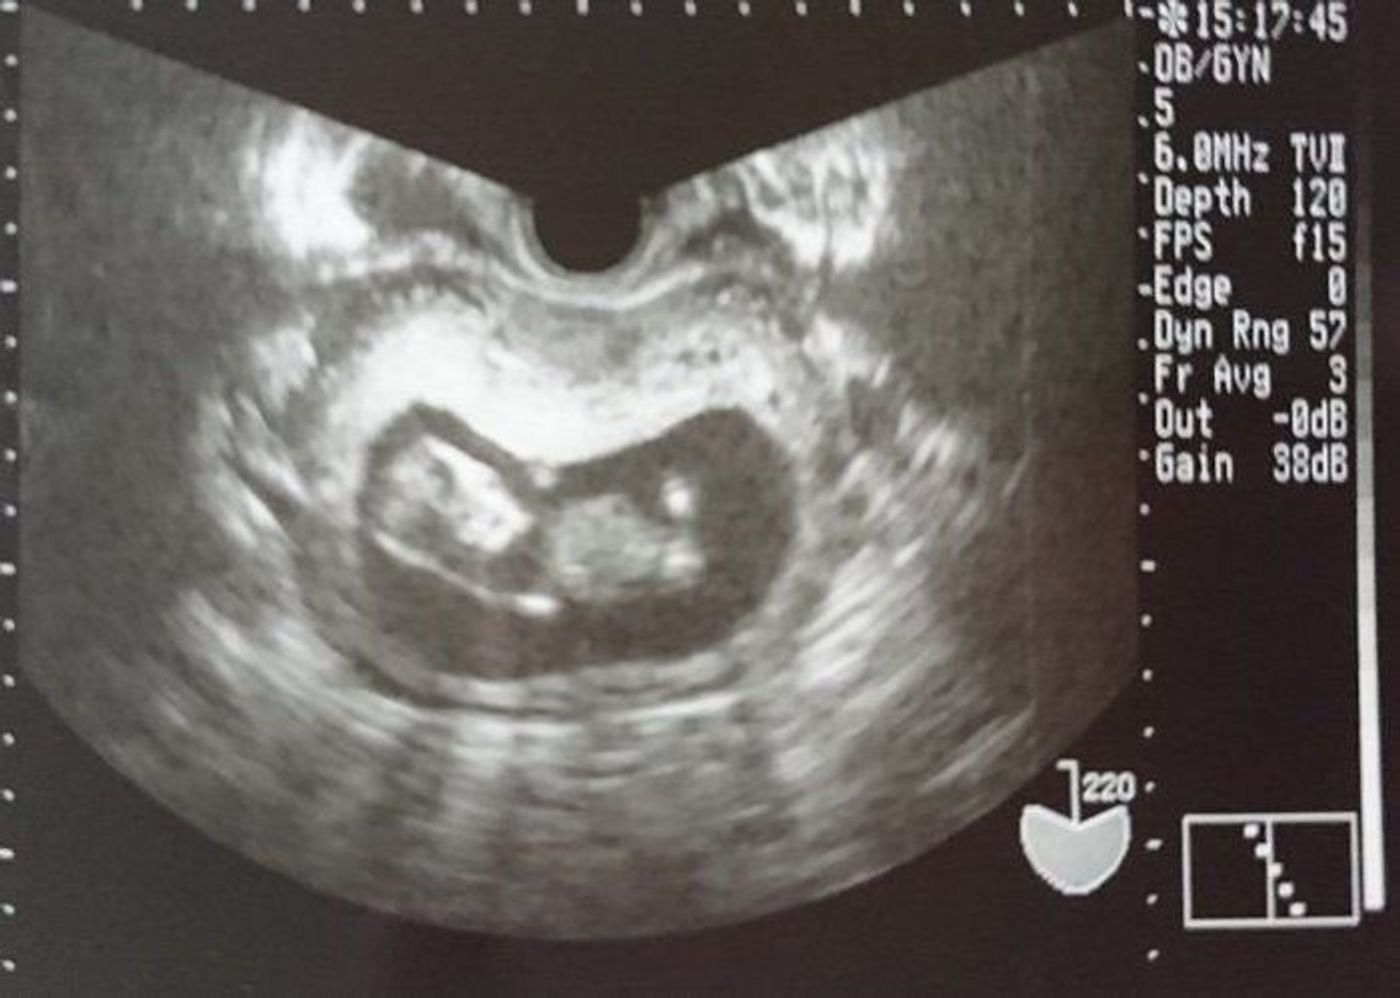

17/9/15 妊娠11週0日目の2Dエコー写真がこちら↓↓ 胎児の大きさ(CRL):413cm そしてそして、妊娠11週0日目の4Dエコー写真がこちら↓↓ ちょっと見にくいかな? 上の2Dエコーの写真と同

11 週 エコー crl-いつからエコーで胎児の舌が大きいかどうか評価できるのかというと大体14週~26週となります。 舌は超音波画像診断で描出しやすい 臓器 です。 巨舌症はBeckwithWiedemann症候群、先天性甲状4/2/18 この日のエコーでは首の後ろの浮腫みと子宮頸管の長さを調べました。 首の後ろに浮腫みがある場合は、心臓に疾患があることが多くダウン症が 疑われることもあります。 妊娠11週前後